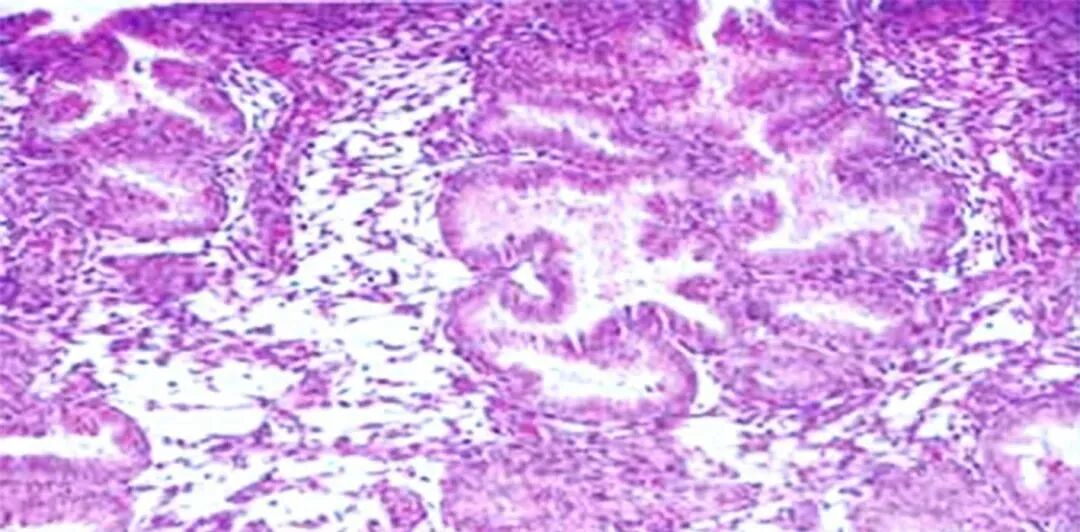

输卵管功能变化

即使没有怀孕史、没有人流手术经历,随着年龄增长,输卵管也可能自然不通。这是因为:

· 感染性疾病(如盆腔炎)的发生率随年龄增加

· 输卵管蠕动功能逐渐减弱

· 内膜容受性下降